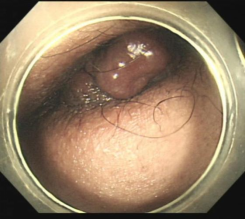

肝硬化食管和胃底静脉曲张破裂出血的内镜下组织胶注射和套扎序惯治疗

混合痔,术前便血和痔疮脱出肛门口,行内痔套扎治疗,解决了出血和痔疮脱出问题。